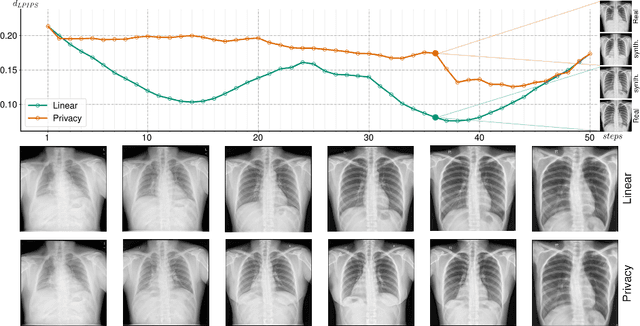

Abstract:Generative Adversarial Networks (GANs) have demonstrated their ability to generate synthetic samples that match a target distribution. However, from a privacy perspective, using GANs as a proxy for data sharing is not a safe solution, as they tend to embed near-duplicates of real samples in the latent space. Recent works, inspired by k-anonymity principles, address this issue through sample aggregation in the latent space, with the drawback of reducing the dataset by a factor of k. Our work aims to mitigate this problem by proposing a latent space navigation strategy able to generate diverse synthetic samples that may support effective training of deep models, while addressing privacy concerns in a principled way. Our approach leverages an auxiliary identity classifier as a guide to non-linearly walk between points in the latent space, minimizing the risk of collision with near-duplicates of real samples. We empirically demonstrate that, given any random pair of points in the latent space, our walking strategy is safer than linear interpolation. We then test our path-finding strategy combined to k-same methods and demonstrate, on two benchmarks for tuberculosis and diabetic retinopathy classification, that training a model using samples generated by our approach mitigate drops in performance, while keeping privacy preservation.